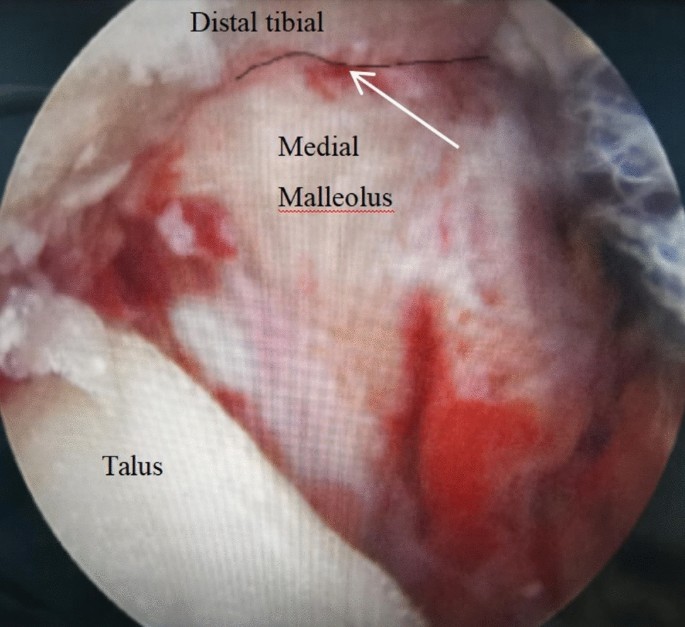

In the ARPF Group: All surgeries were performed under combined spinal-epidura anesthesia in the supine position. The surgical area was sterilised, a pneumatic tourniquet was applied. During the operation, A 2.7 mm, 30°arthroscope (Smith & Nephew, Andover, MA) was inserted into the ankle through a standard anteromedial portal, afterwards the standard anterolateral portal is performed in the same way. The cannula was used to protect tissue and guide the arthroscope into the joint cavity, if the joint space is narrow, an assistant assisted in traction of the ankle joint to increase the joint space. A systematic 21-point arthroscopic examination was performed to assess the articular anatomical structure, intraoperative treatment was performed according to the degree of ligament fiber tear and the depth of cartilage injury(two patients were found to have talar cartilage injury during the operation, The depth of the articular cartilage lesions was graded according to ICRS (International Cartilage Repair Society) arthroscopic grading system, two patients exhibited Grade II talar cartilage injuries, which were managed with microfracture. Partial tear (grade II per Park criteria) of the medial deltoid ligament was found in three patients and were treated with electrocoagulation and tightening. None of the patients had syndesmotic ligament injuries). Before reduction, hemarthrosis and debris were meticulously debrided by a high-speed shaver to expose fracture line (Fig. 1). At the distal end of the medial malleolus, a towel clamp was used to hold the fracture fragment, and with the help of the towel clamp, the fracture fragment was pushed proximally to go near the proximal tibia. Under the monitoring of the arthroscope, a hook needle was used by leveraging or pushing to achieve anatomic reduction. After observing under the arthroscope that the joint surface at the fracture site was smooth, towel clamps were used to temporarily fix both ends of the fracture, at the same time, a K-wire was drilled into the fracture site for temporary fixation. Then, two guide wires were drilled on both sides of the K-wire through the fracture sites, two 3.5 mm cannulated screws were driven over the guidewires (Fig. 2), the length and direction of each screw was measured by using preoperative radiographs and computed tomography scans (Fig. 3). Under the arthroscope, the smoothness of the medial joint was observed and evaluated, and it was checked whether the internal fixators penetrated the joint surface (Fig. 4). Finally, if the length and position of the screw was not certain intraoperatively, fluoroscopy was performed to confirm them.